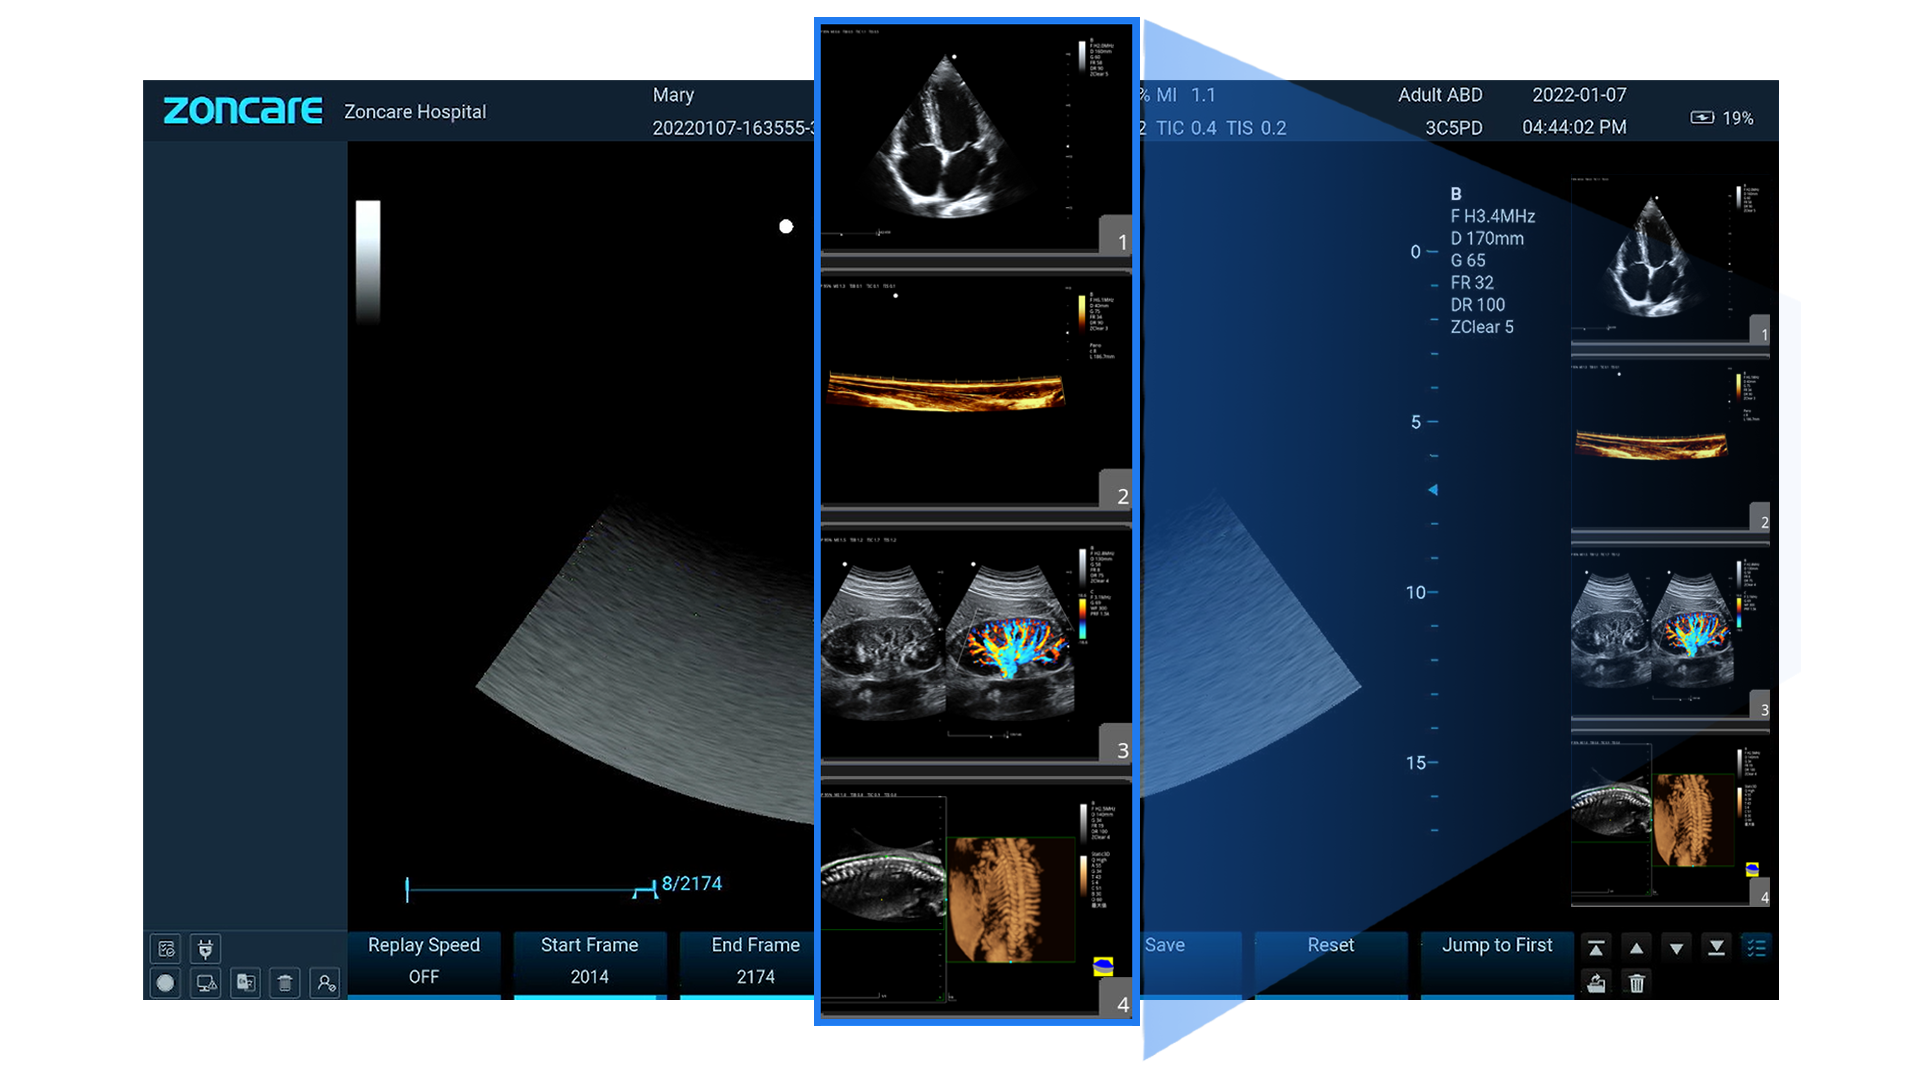

B, B-Steer, M, B/M, 2B/4B

Color Doppler (CDFI), Power Doppler (PDI/DPDI)

Doppler Pulsado (PW) y Continuo (CW)

Anatomic M (recto y curvo)

TDI (TVI, TVD, TVM, TEI)

Panorámico y Color Panorámico (EFOV)

Elastografía

3D / 4D (ZLive, Silhouette)

Formatos: RAW, DICOM, JPG, BMP, TIFF, AVI, MP4